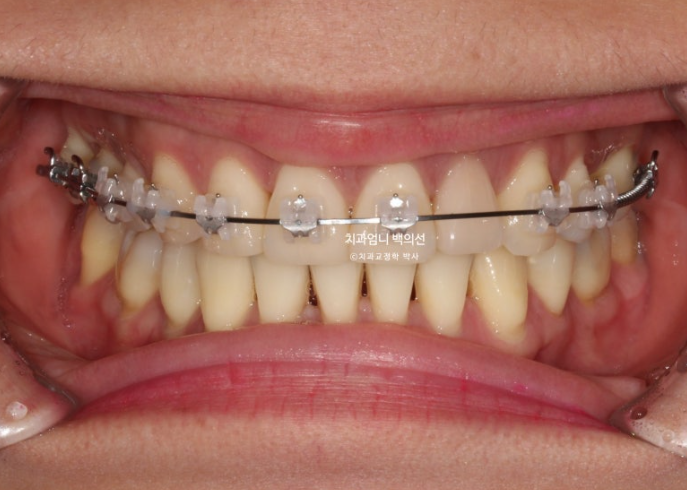

23년 8월, 재교정치료를 위해 내원한 환자분입니다.

23.08

블랙트라이앵글과 중심선 불일치가 보입니다.

잇몸이 얇은 편이라 작은어금니 부분에 잇몸퇴축도 보입니다.

얼굴에 비해 위 앞니 중심선이 좌측으로 돌아간 상태인데

원인은 좌우 치아 갯수 차이에 있었습니다.

오래 전 했던 발치교정으로 작은어금니 4개가 없는 상태인데 좌측 첫번째 큰어금니 1개가 추가로 더 없습니다.

상악 좌측에만 치아갯수가 2개나 없는거죠.